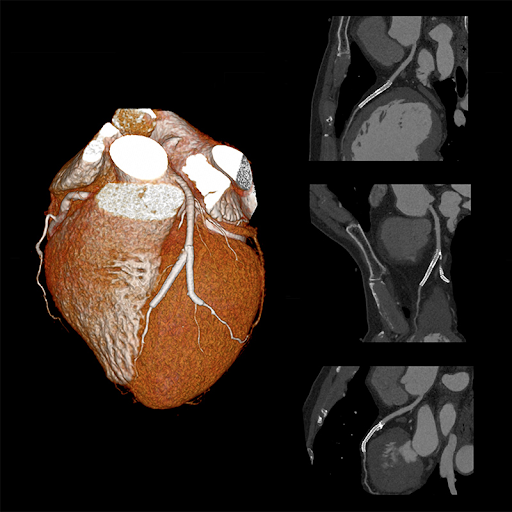

Визуализация сердца